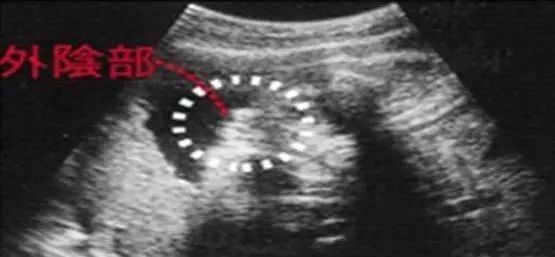

女宝宝的b超图

三条白线是明显的女宝特征,如果没有看到明显的三条白线,就看两腿之间有没有突出的东东,且中间有小凹槽的,就是女宝。